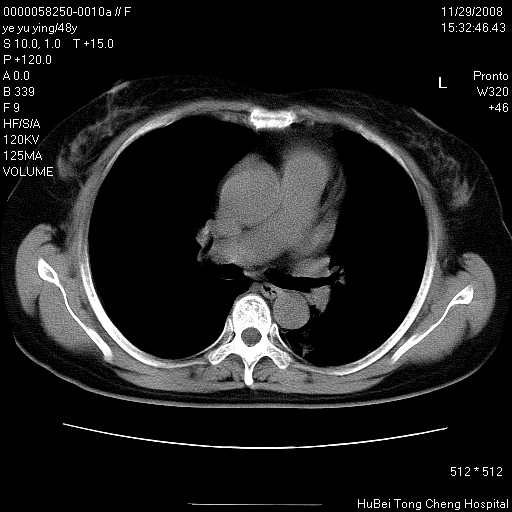

以下是引用zsl6918在2008-11-29 21:47:00的发言:[br]恶性肿瘤病史,转移瘤首先考虑。脂肪肝,胆囊结石。

以下是引用huenhao在2008-11-29 22:11:00的发言:[br]脂肪肝,胆囊结石。左肺病灶建议定期复查。

以下是引用liuyue在2008-11-30 5:44:00的发言:[br]1.左肺病变,首先考虑感染性病变,转移待排;建议治疗后复查。[br]2.肝脏密度普遍减低,考虑与化疗有关。[br]3.胆囊结石.